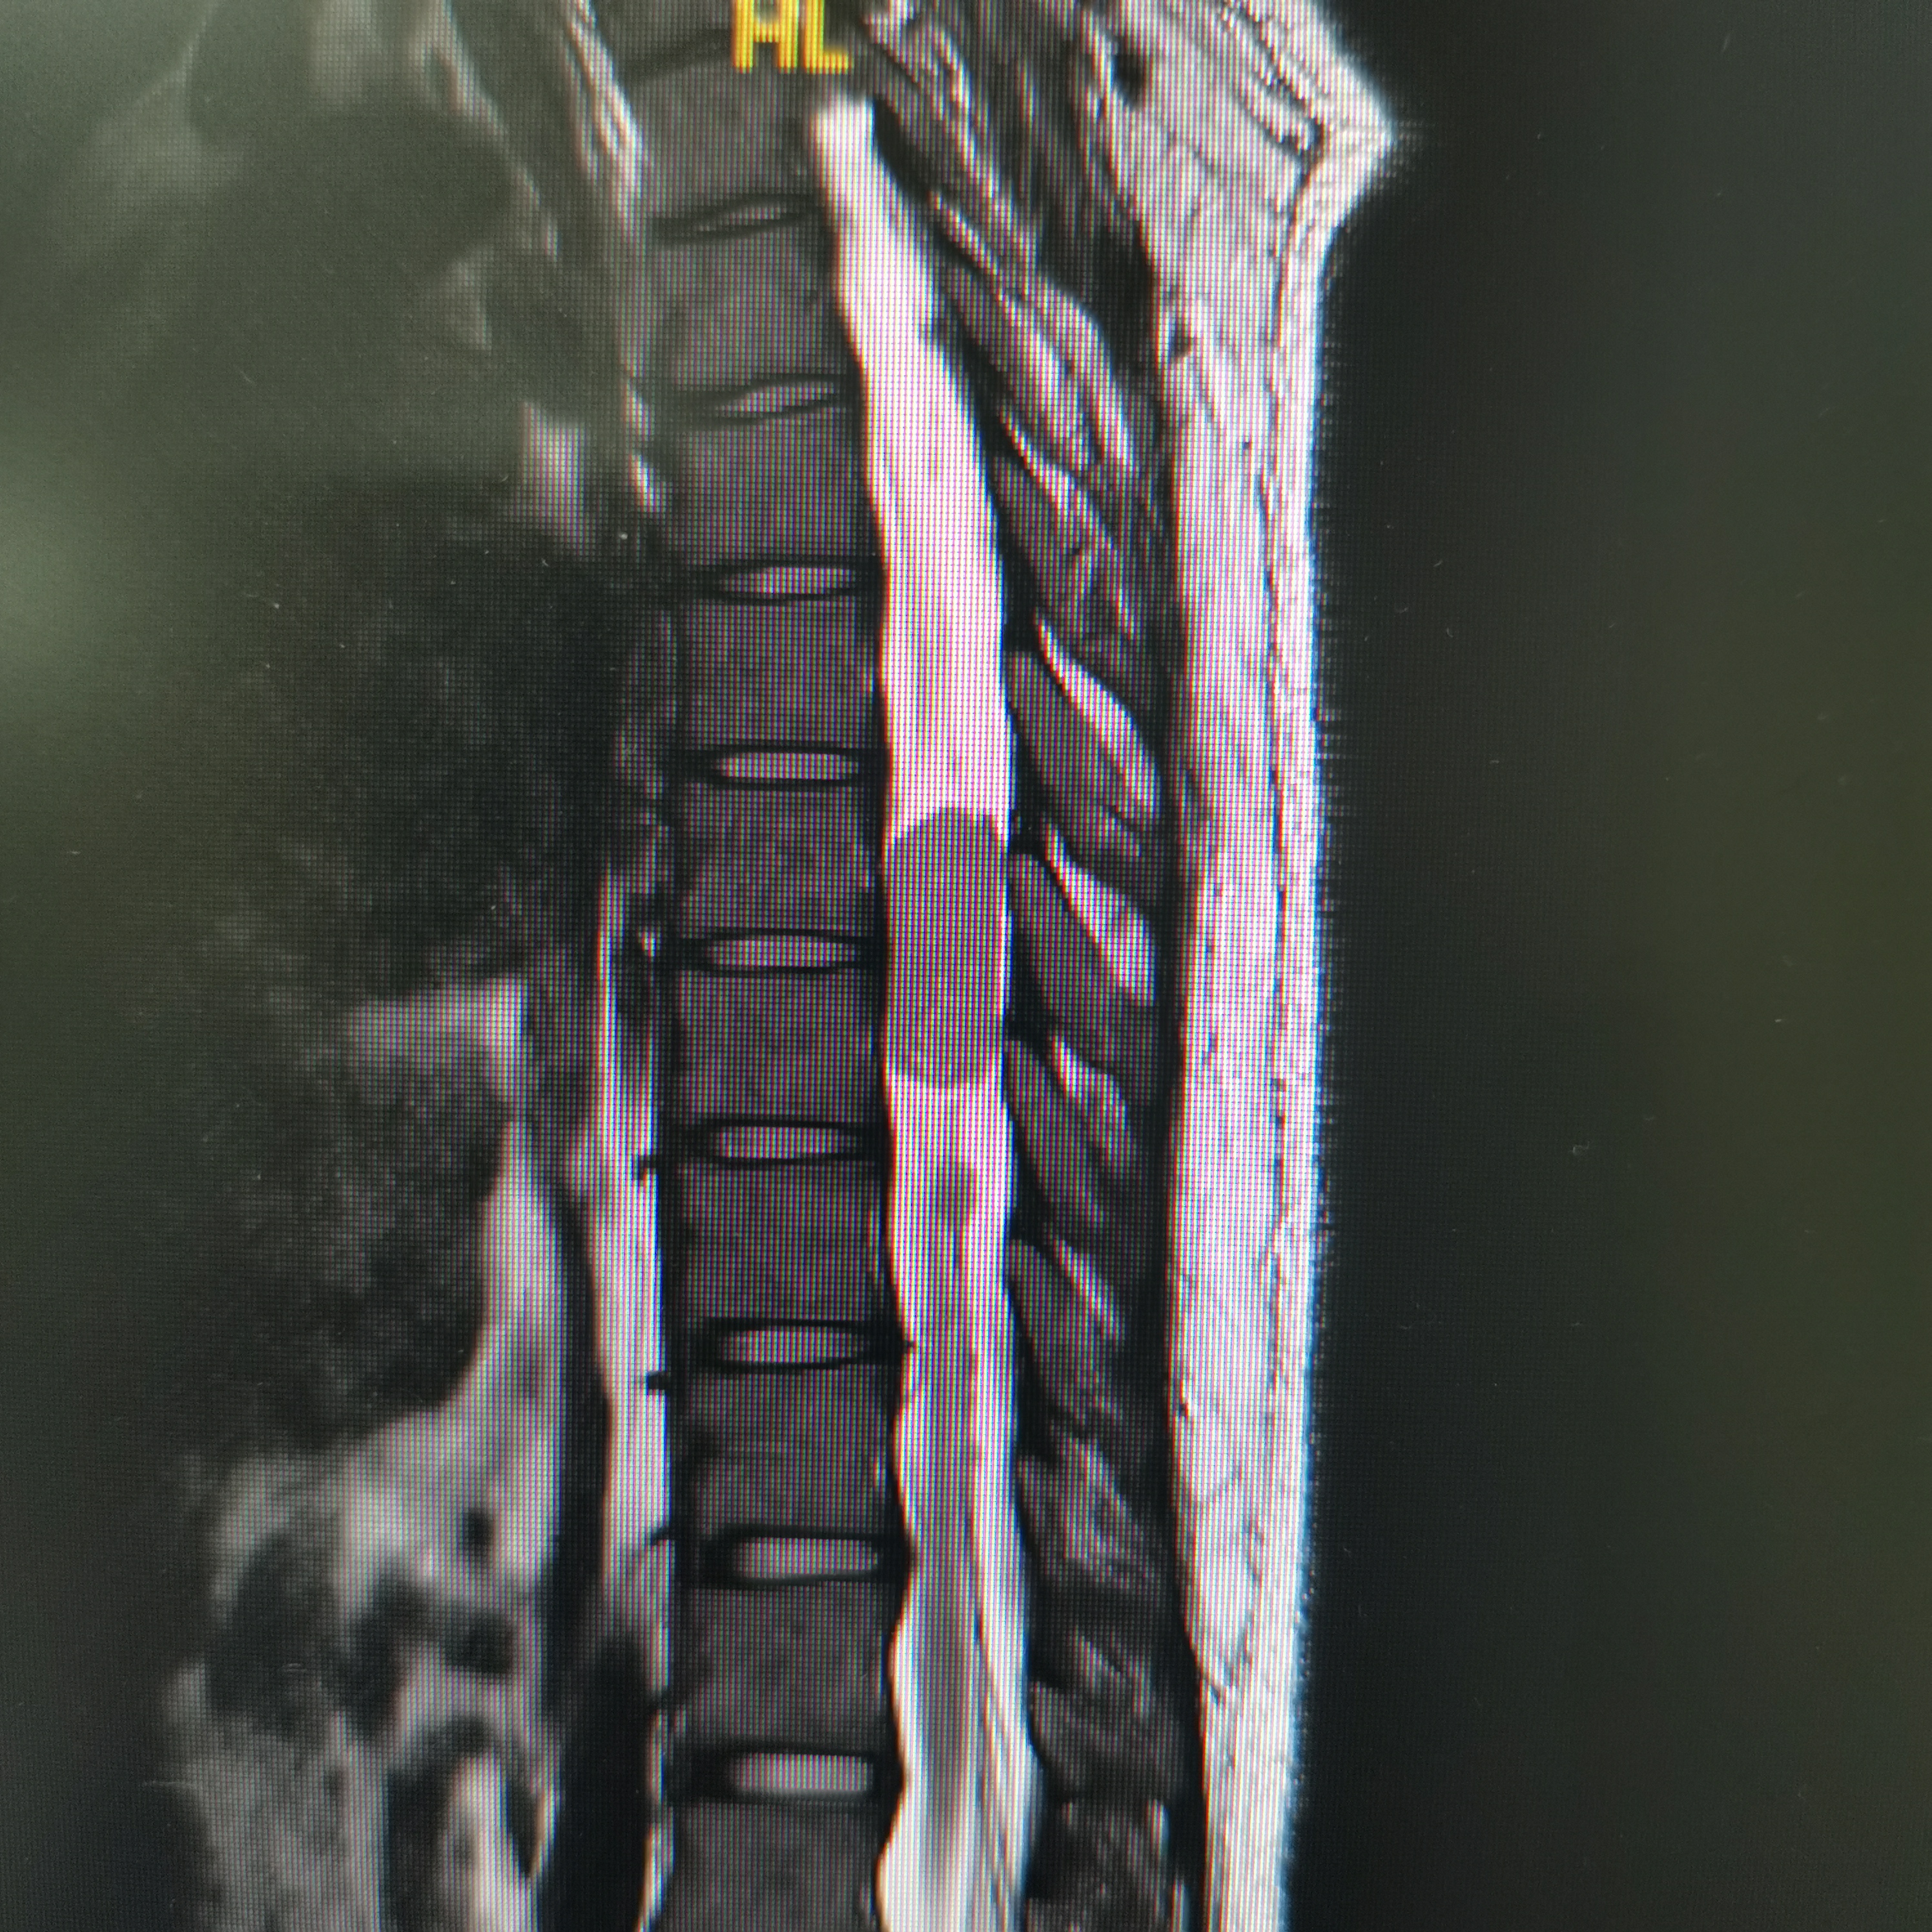

脊髓脊柱-脊髓脊柱肿瘤

神经纤维瘤病的治疗需要综合考虑患者的病情、症状、年龄、身体状况等因素,制定个性化的治疗方案。